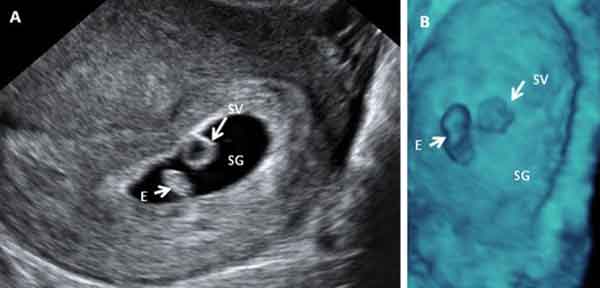

Embarazo de 7 semanas en 2D y 3D

La longitud del embrión es de 8 milímetros. Tanto en la ecografía en dos dimensiones (a la izquierda A), como en la ecografía 3D (a la derecha B), es posible ya visualizar el embrión (E) separado del saco vitelino (SV).